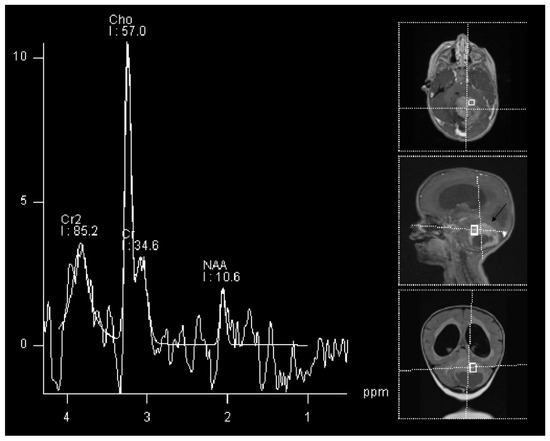

- Kazda, T.; Bulik, M.; Pospisil, P.; Smrcka, M.; Slampa, P.; Jancalek, R. Advanced MRI increases the diagnostic accuracy of recurrent glioblastoma: Single institution thresholds and validation of MR spectroscopy and diffusion weighted MR imaging. NeuroImage Clin. 2016, 11, 316–321. [Google Scholar] [CrossRef]

- Smith, E.; Carlos, R.; Junck, L.; Tsien, C.; Elias, A.; Maly Sundgren, P. Developing a Clinical Decision Model: MR Spectroscopy to Differentiate Between Recurrent Tumor and Radiation Change in Patients with New Contrast-Enhancing Lesions. AJR Am. J. Roentgenol. 2009, 192, W45–W52. [Google Scholar] [CrossRef]

- Elias, A.E.; Carlos, R.C.; Smith, E.A.; Frechtling, D.; George, B.; Maly, P.; Sundgren, P.C. MR Spectroscopy Using Normalized and Non-normalized Metabolite Ratios for Differentiating Recurrent Brain Tumor from Radiation Injury. Acad. Radiol. 2011, 18, 1101–1108. [Google Scholar] [CrossRef]

- Bulik, M.; Kazda, T.; Slampa, P.; Jancalek, R. The Diagnostic Ability of Follow-Up Imaging Biomarkers after Treatment of Glioblastoma in the Temozolomide Era: Implications from Proton MR Spectroscopy and Apparent Diffusion Coefficient Mapping. BioMed Res. Int. 2015, 2015, 641023. [Google Scholar] [CrossRef]

- Zeng, Q.S.; Li, C.F.; Liu, H.; Zhen, J.H.; Feng, D.C. Distinction Between Recurrent Glioma and Radiation Injury Using Magnetic Resonance Spectroscopy in Combination with Diffusion-Weighted Imaging. Int. J. Radiat. Oncol. Biol. Phys. 2007, 68, 151–158. [Google Scholar] [CrossRef] [PubMed]